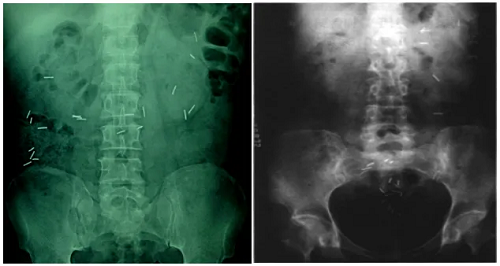

结肠传输试验:接受胃肠标记胶囊检查的患者,口服不透X线的标志物,分别于24小时、48小时、必要时72小时拍摄腹部平片,追踪观察标志物在结肠内运行的部位、时间,是判断结肠内容物运行的速度及受阻部位的一种诊断方法,有助于评估便秘是动力减弱的慢传输,还是肛门直肠异常导致的出口梗阻。

注:口服标志物后48小时腹平片,左图标志物大部分位于乙状结肠以上为慢传输型;右图大部分存留在左半结肠为出口梗阻型。